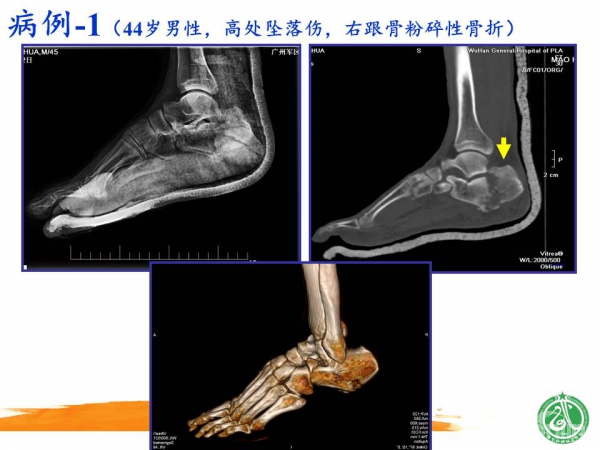

2015-01-12 文章来源:广州军区武汉总医院骨科 魏世隽 我要说